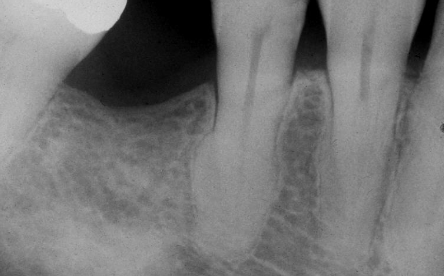

hereditary condition affecting dentin, AD, both dentitions affected, 2-types (coronal and radicular)

dentin dysplasia (DD)

DD-I

radicular dentin dysplasia

4 types, normal clinical crown, short roots, periapical radiolucencies, chevron pulp chambers